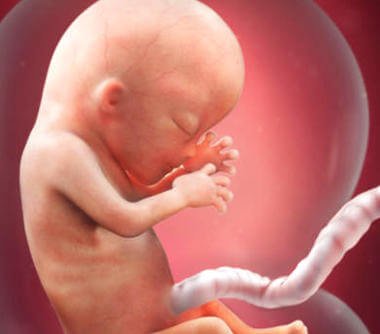

In der 13. Schwangerschaftswoche liegt die Größe des Babys schon bei ungefähr 6,5-10 cm und es hat ein Gewicht von 13-20 Gramm. Sein Körper macht in dieser Zeit viele Veränderungen durch und in seinem Gesicht zeigen sich nun die ersten unverwechselbaren Merkmale – wie aufregend!

Neben den erkennbaren Gesichtszügen gibt es aber auch noch ein anderes faszinierendes Detail: Die Fingerabdrücke haben sich entwickelt!

Das Gehirn ist zu diesem Zeitpunkt eines der meist entwickelten Körperteile. Aber auch die Strukturen, die die inneren Organe abdecken und schützen zählen dazu.

Der Kopf des Kindes macht nun noch die Hälfte der gesamten Körpergröße aus. Doch schon bald beginnt der Rest des Körpers zu wachsen. Stück für Stück formen sich so die “normalen” Proportionen des Körpers. Bei der Geburt wird der Kopf nur noch ein Viertel der gesamten Körpergröße ausmachen. Aber es gibt auch einige andere Prozesse, die nun beginnen und die für den Körper des Babys und seine Funktionsweise sehr wichtig sind.